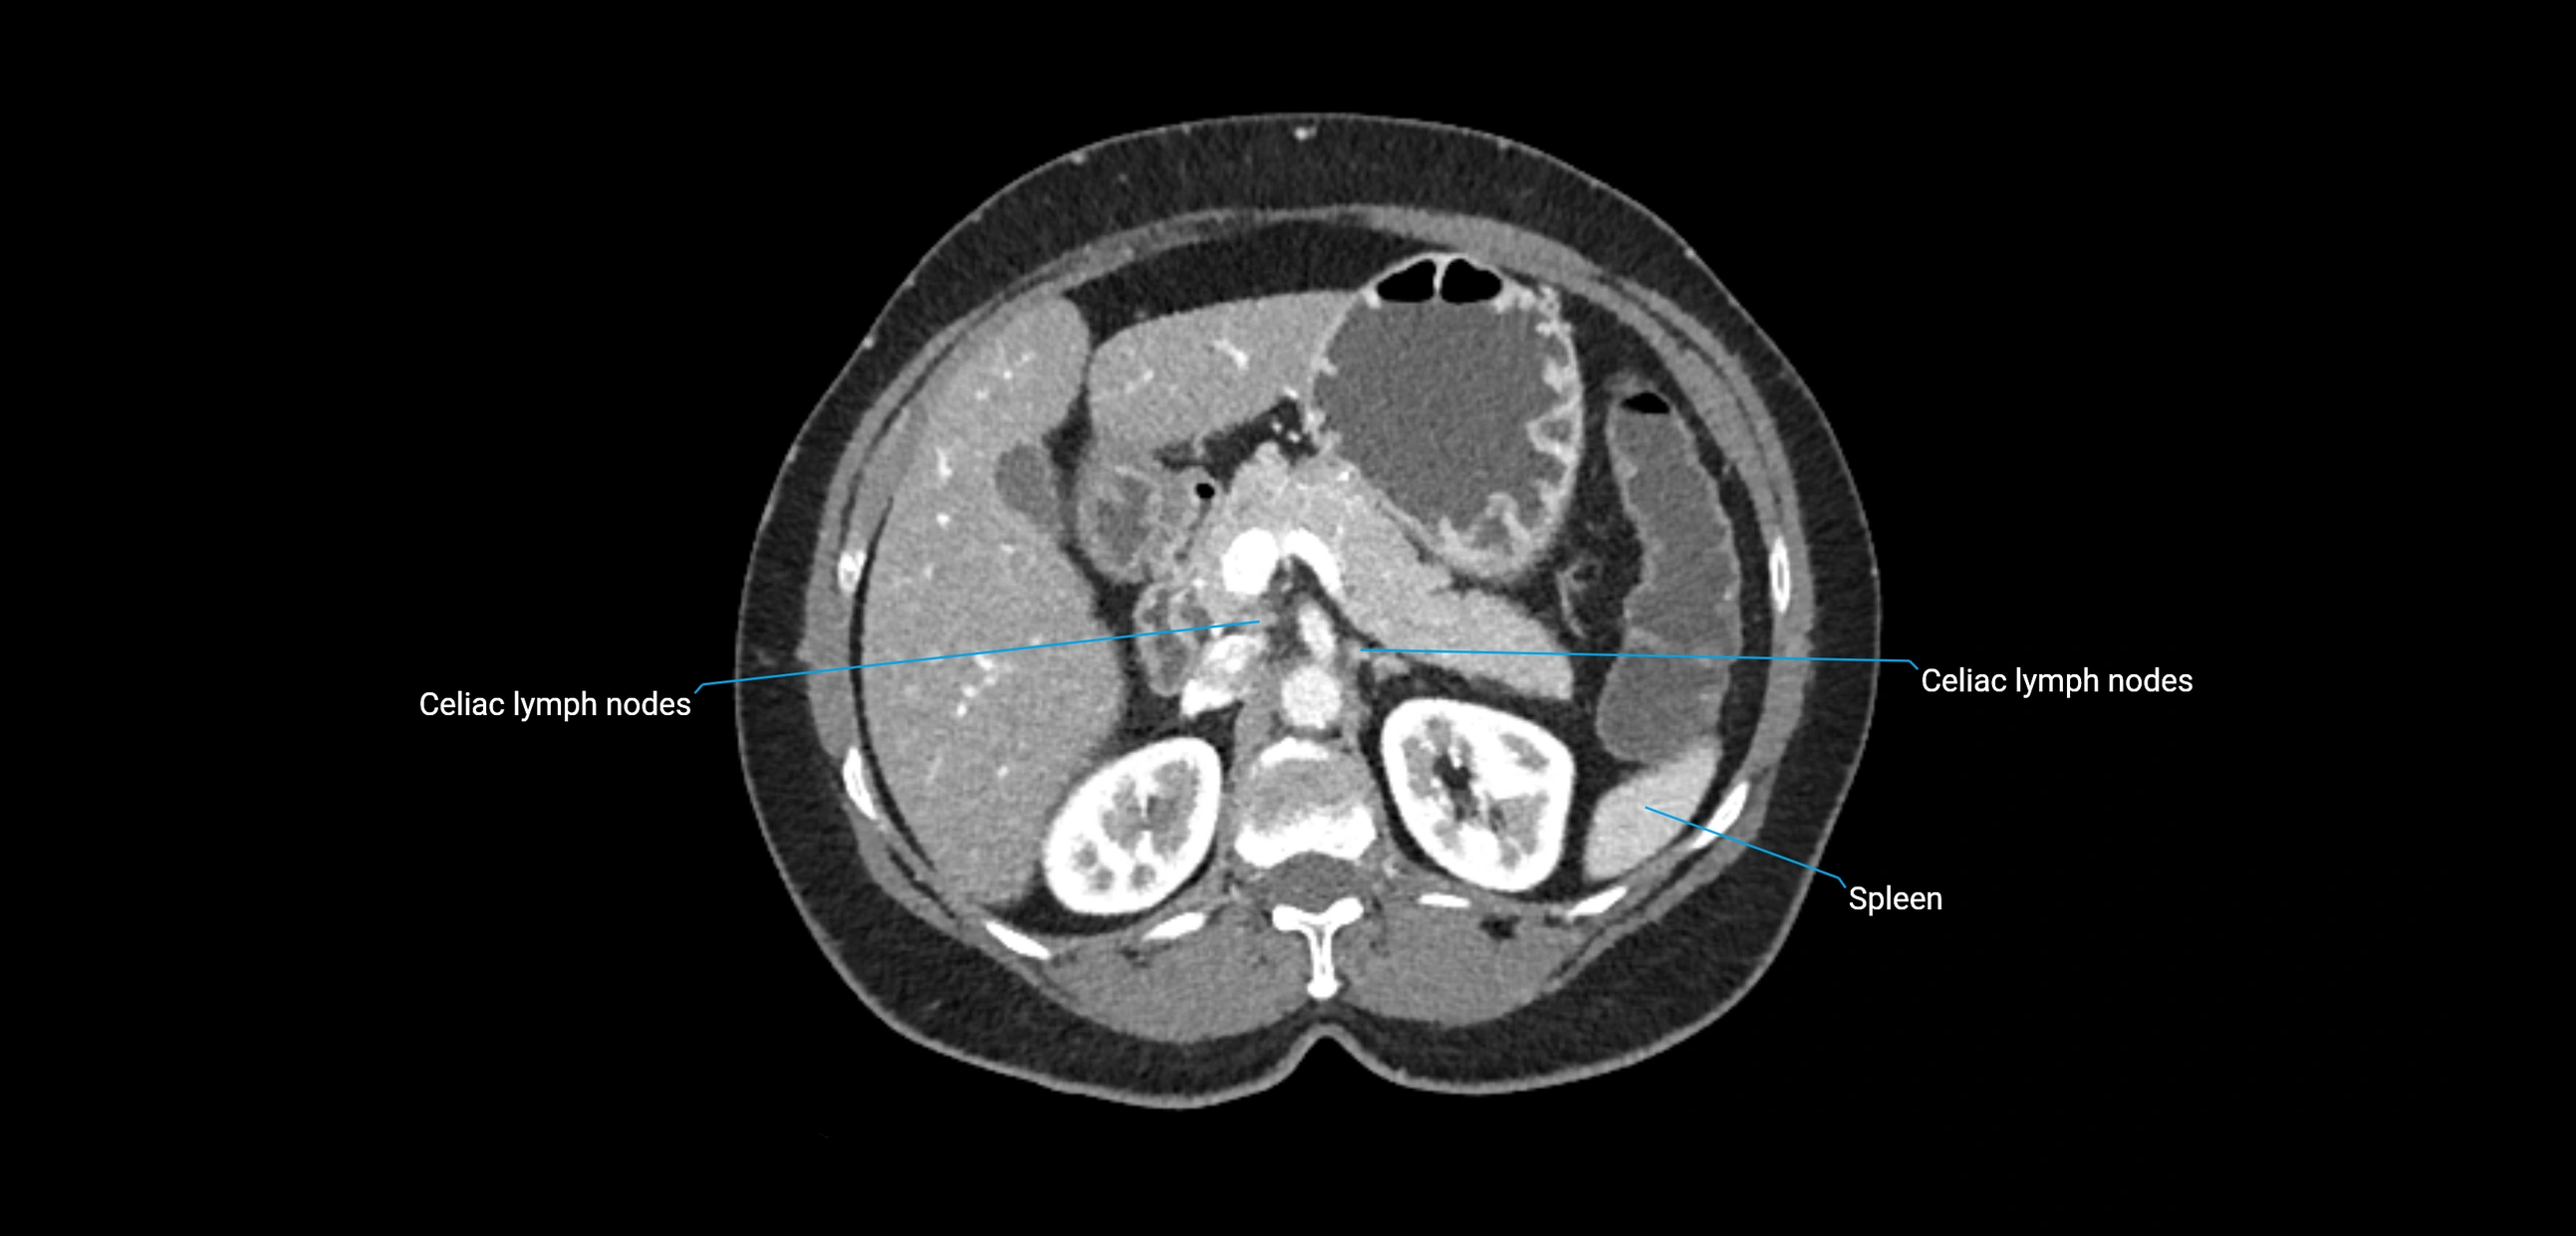

MRI images

image